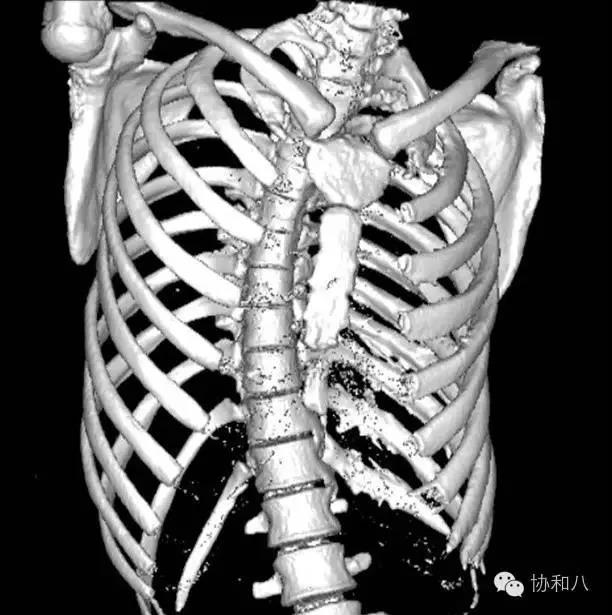

胸部 CT+肋骨重建:胸膜弥漫性增厚伴多发结节,肋骨骨膜反应明显,胸膜间皮瘤可能,脊柱侧弯。

全身骨显像:四肢长骨及左侧肋骨放射性摄取增高,四肢长骨骨皮质增厚。

累及胸膜者:间质纤维组织增生伴胶原化钙化,以致胸膜肥厚,纤维板性粘连,胸腔消失。